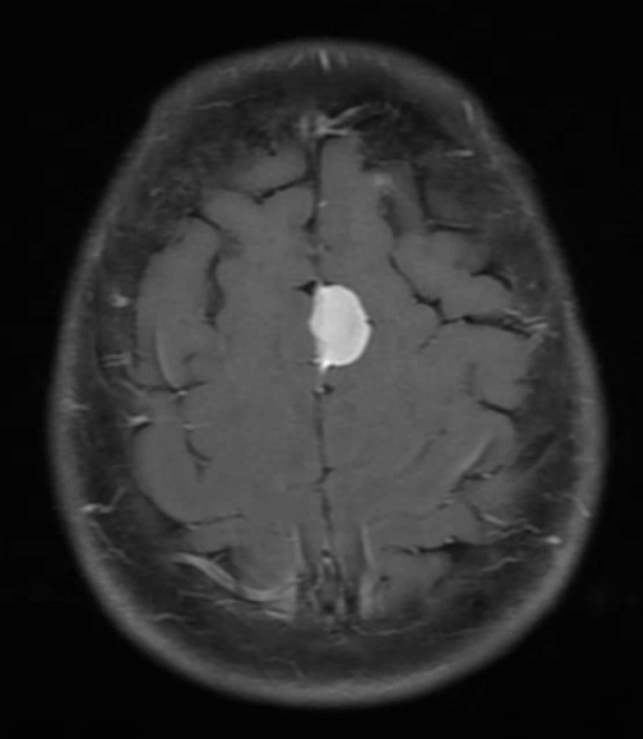

What are the imaging findings:

Scolex: part of tanea solium worm that attaches with 4 suckers along with an engancing lesion with vasogenic edema (consistent with degenerating cyst).